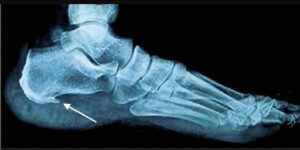

La spina calcaneare, scientificamente nota come entesite calcifica, rappresenta una condizione ortopedica diffusa, caratterizzata dalla deposizione di sali di calcio all’origine dei tendini nella fascia